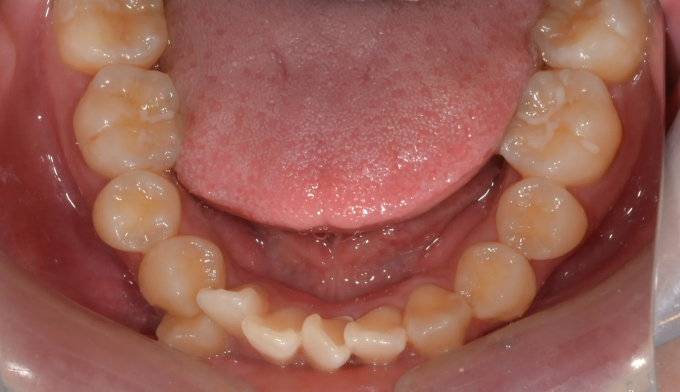

덧니를 해소하기 위해 필요한 공간의 양도 매우 많으며, 돌출의 정도도 심한편입니다. 또한 개방교합도 존재하고 있으며, 악궁의 폭도 매우 좁은편입니다.

성인에서 기존의 앞니 치열이 매우 고르지 못하면, 교정 이후에 아래 앞니와 같은 블랙트라이앵글이 생길 수 있습니다. 마무리 교정 시 원한다면 해당 공간의 크기를 줄일 수 있습니다.